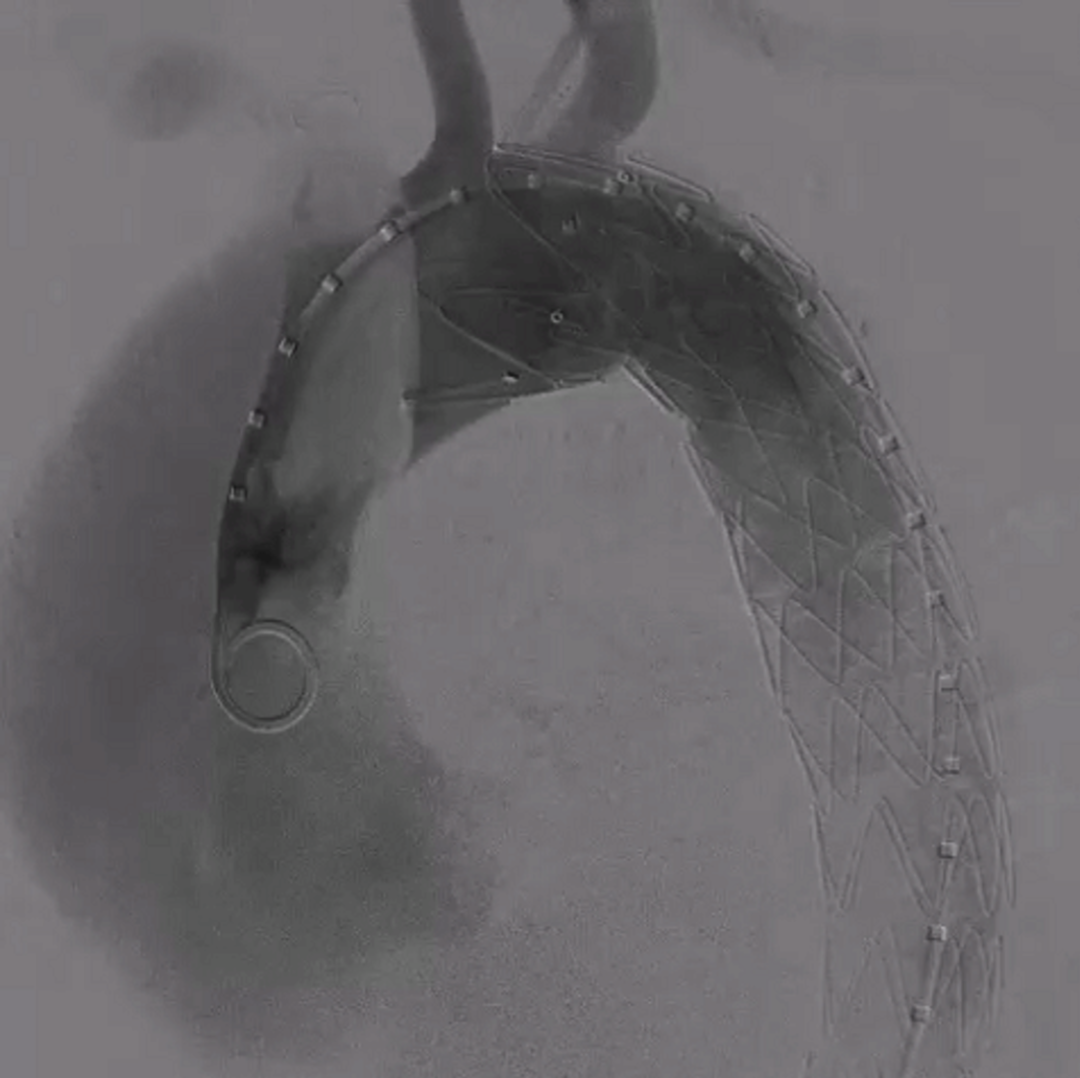

【病例2】主动脉B型夹层,

2016年外院TEVAR术后II型内漏

术后8年随访发现假腔明显扩大,最大直径达96mm,伴胸背疼痛,有手术干预指征。

再干预方案:弹簧圈栓塞分支血管(LSA栓塞),覆膜支架+封堵器+弹簧圈覆盖左肾动脉破口。

修复结果:进入假腔血流明显减少,胸背疼痛症状明显缓解。

二次手术前CTA